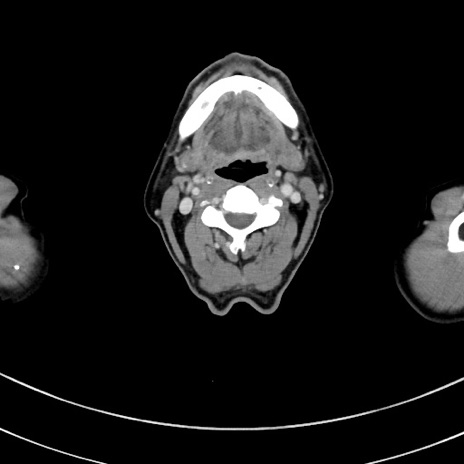

症例8(横断像)

【症例】 60歳代男性

【主訴】 黒色吐物

【現病歴】 4日前から嘔気自覚、2日前の朝食後にも嘔気あり、自分で手で嘔吐反射起こし嘔吐したところ血が混ざっていたため受診。

【既往歴】 5年前汎発性腹膜炎を伴う急性虫垂炎で手術、高血圧、前立腺肥大症、高脂血症

【身体所見】 腹部正中に手術癩痕あり 腹部平坦・軟圧痛なし膨満感あり

【データ】WBC 8400、CRP 4.54